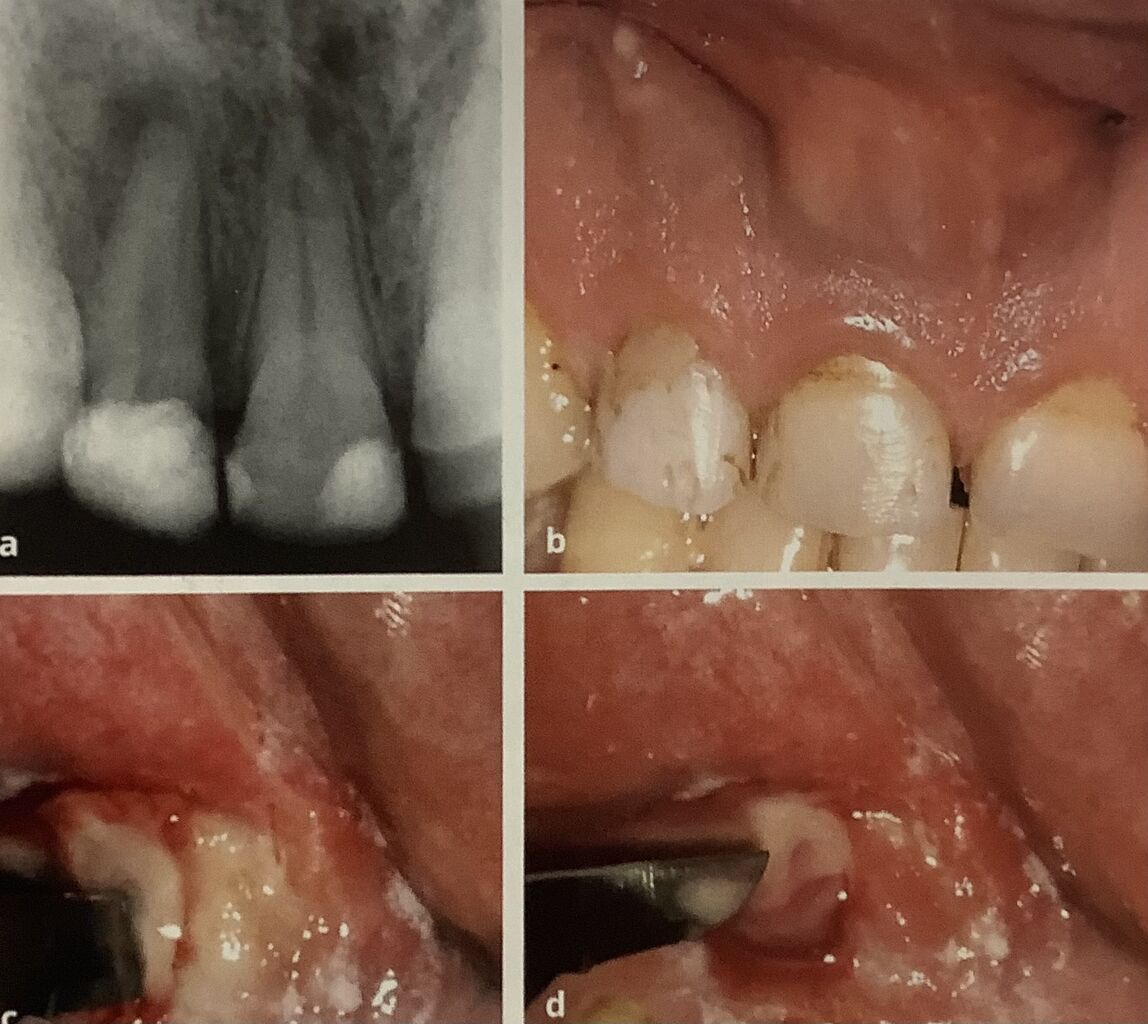

根元にある水ぶくれを切開して膿を出しています。